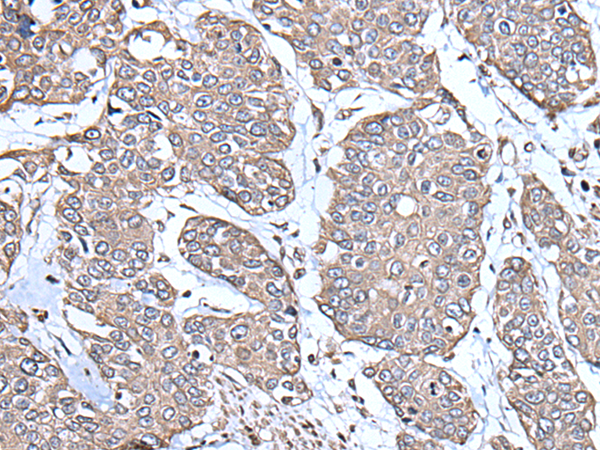

分类: 科研抗体货号: P08616别名: MPR; HPR6.6应用: WB,IHC反应种属: Human, Mouse, Rat

分类: 科研抗体货号: P08628别名: SAK; STK18; MCCRP2应用: IHC反应种属: Human, Mouse, Rat